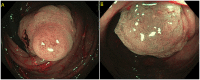

Most colorectal cancers arise from adenomatous polyps and sessile serrated lesions. Screening colonoscopy and therapeutic polypectomy can potentially reduce colorectal cancer burden by early detection and removal of these polyps, thus decreasing colorectal cancer incidence and mortality. Most endoscopists are skilled in detecting and removing the vast majority of polyps endoscopically during a routine colonoscopy. Polyps can be considered "complex" based on size, location, morphology, underlying scar tissue, which are not amenable to removal by conventional endoscopic polypectomy techniques. They are technically more challenging to resect and carry an increased risk of complications. Most of these polyps were used to be managed by surgical intervention in the past. Rapid advancement in endoscopic resection techniques has led to a decreasing role of surgery in managing these complex polyps. These endoscopic resection techniques do require an expert in the field and advanced equipment to perform the procedure. In this review, we discuss various advanced endoscopic techniques for the management of complex polyps.